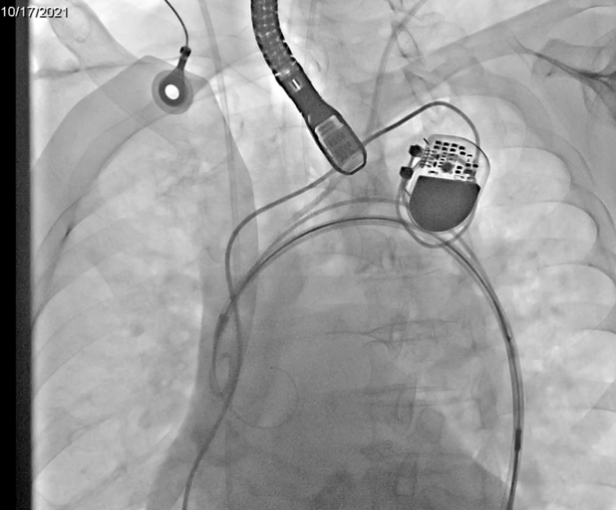

患者为女性,85岁,2013年行冠脉支架植入术,2018年再次行冠脉支架植入术合并房颤冷冻球囊消融术,2020年行永久起搏器植入术。1年前无明显诱因出现间断活动后气促,活动耐力下降,近3月上述症状加重。术前CT显示主动脉瓣为三叶瓣,重度钙化,术前经胸超声主动脉瓣口峰值流速5.7m/s,峰值压差124mmHg,平均跨瓣压差78mmHg,诊断为主动脉瓣重度狭窄伴关闭不全。

经过专家术前详细讨论,一致认为该患者符合Leaflex™ Performer经导管主动脉瓣膜修复系统的手术指征。

1. 术中在进行修复时,关注患者血流动力学变化情况;

2. 使用远端脑保护装置,避免脑栓塞发生;